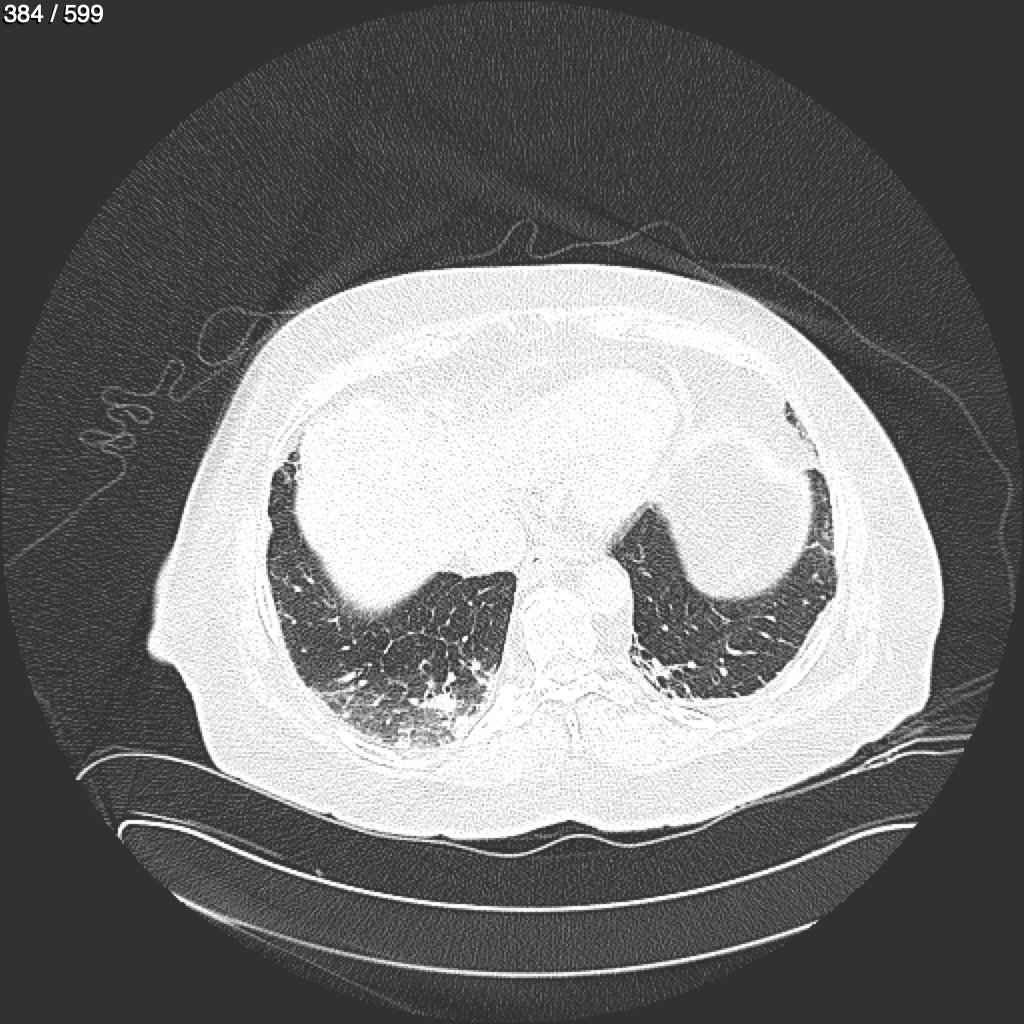

Home G​l​o​r​i​a​ ​G​l​a​d​y​s​ ​B​e​a​s​l​e​y​ ​-​ ​T​ó​r​a​x​ ​T​o​r​a​x​_​S​i​m​p​l​e​ ​(​A​d​u​l​t​o​)